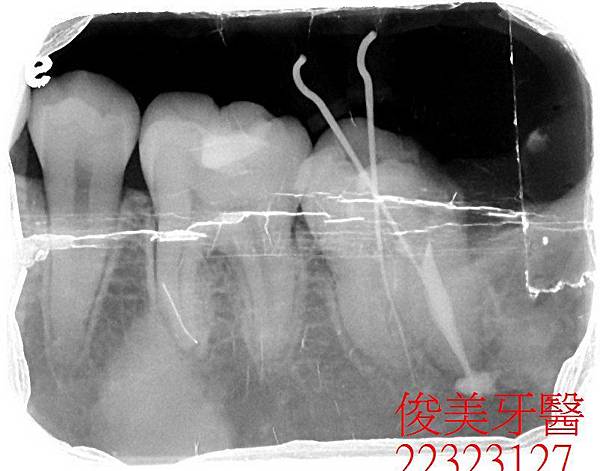

患者為女性,年約25歲,於門診時表示,左下牙齒在其他地方治療後仍會疼痛,於是在搜尋資料後

,找到我們診所,希望可以諮詢醫師的意見;經醫師檢查後發現,左下第二大臼齒根尖有狀況,且

牙齒破損嚴重,加上患者症狀已持續一段時間,此顆牙齒位置及角色重要,但牙齒所剩價值卻不多

,因此建議患者將此顆牙齒拔掉根治。

患者同意了,因她確實在其他地方處理多次,但效果不彰。

拔出後,明顯可見,牙齒蛀牙面積已太大,既使將來做牙套,強度也會減弱不少。拔除後患者表示

,再也不痛了。